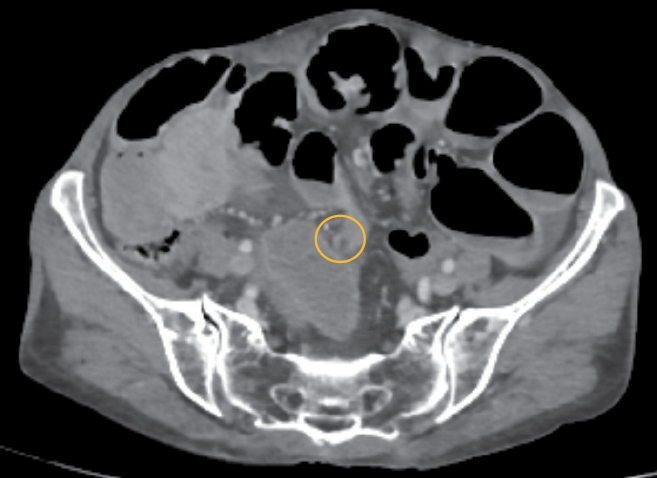

Figure 2. CECT Abdomen & Pelvis showing transition point at the level of distal ileum

Contrast Enhanced Computed Tomography (CECT Abdomen & Pelvis) was suggestive of acute intestinal obstruction with possible transition point in distal ileum (approx. 10 cm from ileo colic junction) with bowel loops showing normal enhancement pattern and no evidence of perforation. Free fluid was noted in the peri-hepatic, peri splenic, hepato renal pouch inter bowel space and pelvis (Figure 2).